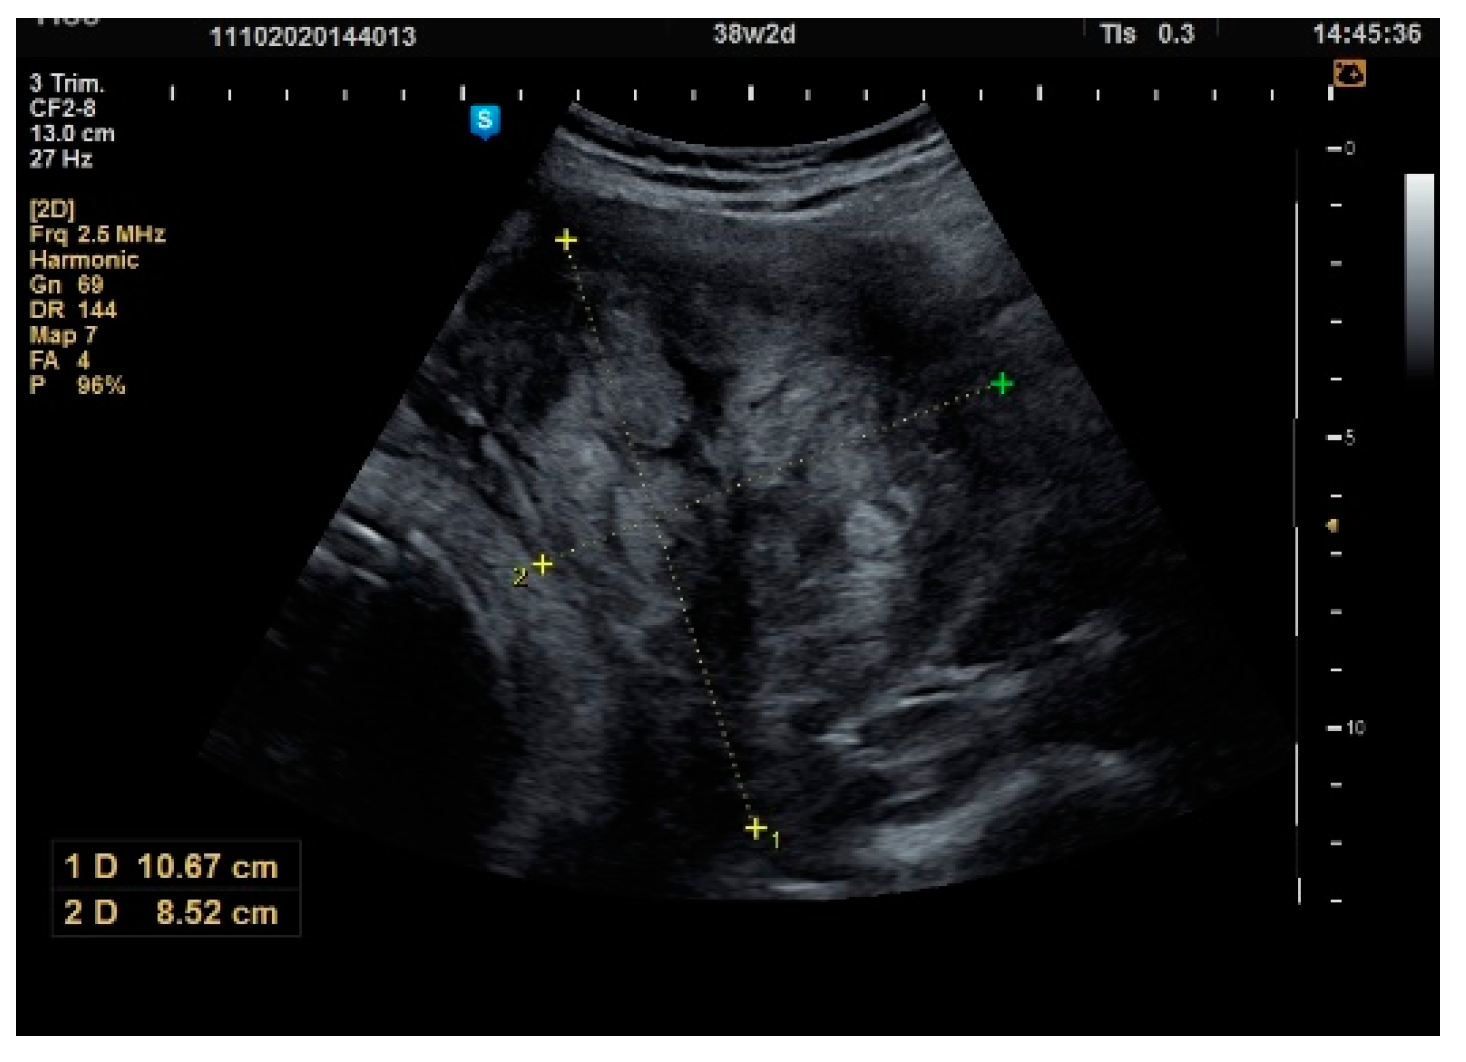

| Antepartum | 1st Trimester | 2nd Trimester | 3rd Trimester | |

| N | 55 | 49 | 50 | 53 |

| Mean | 40.02 | 44.51 p = 0.005 * | 54.76 p = 0.001 * | 61.58 p = 0.001 * |

| Difference from the previous average | - | +4.49 mm (+11.2%) | +10.25 mm (+23.0%) | +6.92 mm (+12.6%) |

| Median | 38 | 40 | 50 | 60 |

| Std. Deviation | 18.29 | 17.21 | 21.37 | 24.54 |

| Variance | 42.88 | 38.67 | 39.04 | 39.59 |

| Skewness | 0.970 | 0.733 | 0.664 | 1.636 |

| Std. Err. of Skewness | 0.322 | 0.340 | 0.337 | 0.327 |

| Minimum | 20 | 20 | 20 | 25 |

| Maximum | 90 | 90 | 100 | 160 |

| 25th percentile | 23 | 30 | 40 | 48 |

| 50th percentile | 40 | 40 | 50 | 60 |

| 75th percentile | 50 | 50 | 64 | 70 |